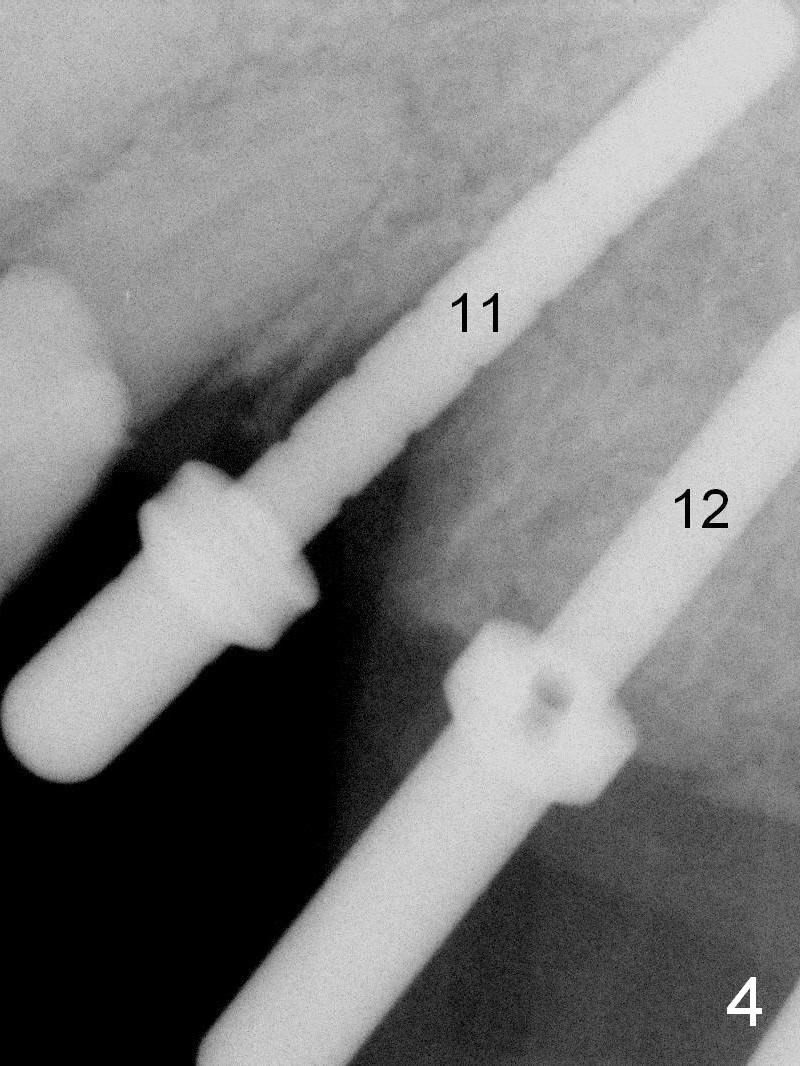

Parallel pins are inserted for trajectory confirmation (Fig.4).